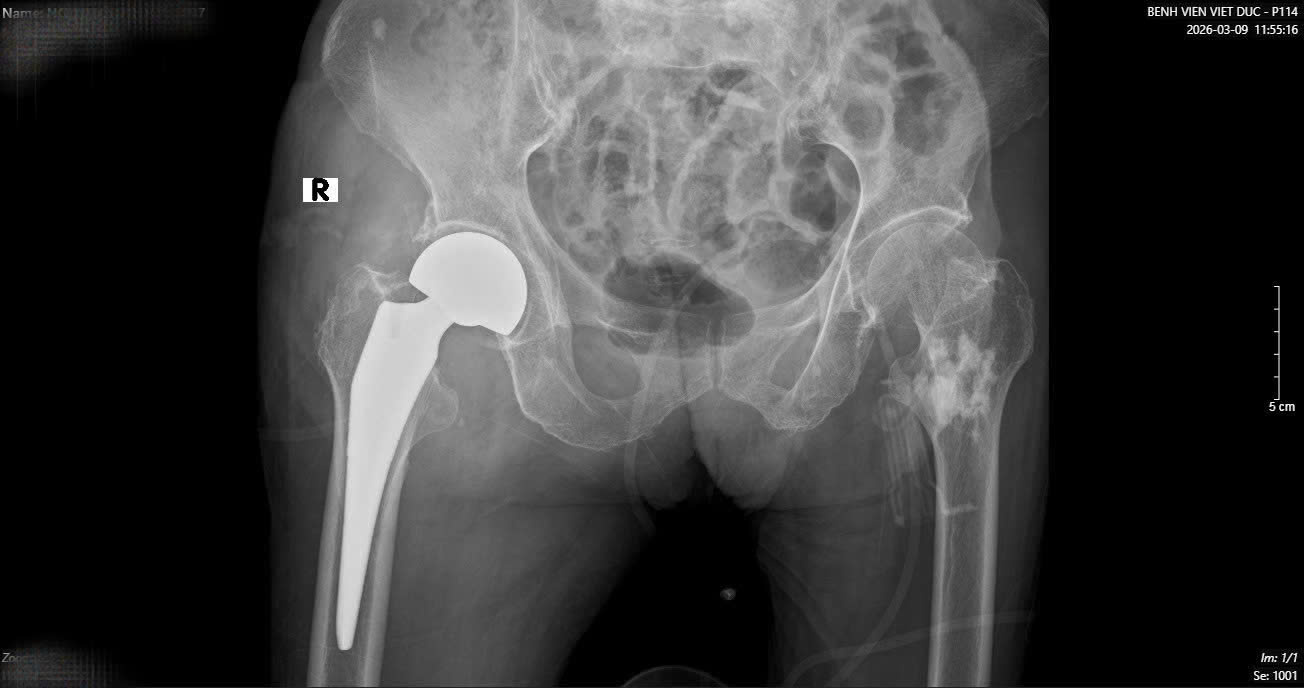

Sau một tuần, khi các chỉ số sức khỏe ổn định, cụ bà tiếp tục bước vào cuộc đại phẫu thứ hai. TS.BS Hoàng Ngọc Sơn đã trực tiếp phẫu thuật thay khớp háng cho cụ. Nhờ sự chuẩn bị kỹ lưỡng của đội ngũ y bác sĩ, ca mổ đã thành công tốt đẹp.

Chỉ sau một tuần thay khớp, cụ bà đã có thể tập đi và vận động gần như bình thường. Đây là kết quả rất khả quan đối với một bệnh nhân cao tuổi vừa trải qua hai cuộc đại phẫu liên tiếp trong vòng 16 ngày.

Chỉ sau một tuần thay khớp, cụ bà đã có thể tập đi và vận động gần như bình thường.